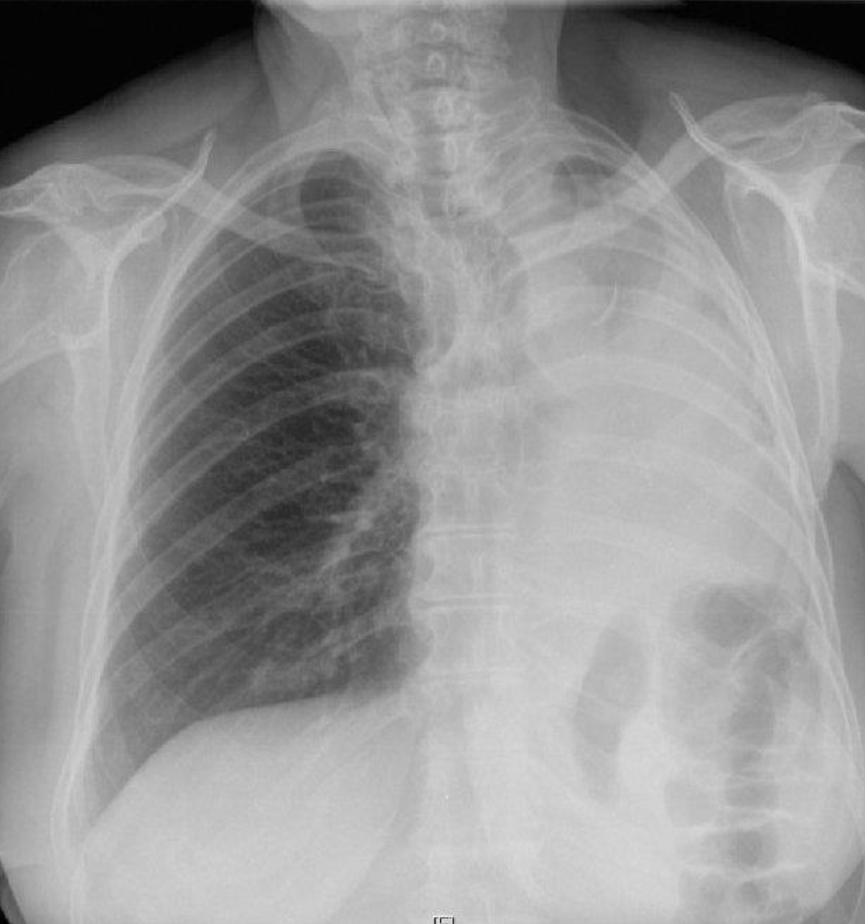

- The left hemithorax is opaque

- There is no shift of the heart or trachea

- The opacified hemithorax contains air bronchogram

- No loss of lung volume